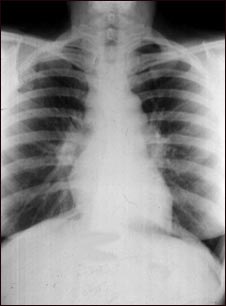

Sarcoidosis, estado I - radiografía de tórax

La sarcoidosis es principalmente una en enfermedad pulmonar. Cuando se encuentra en sus etapas tempranas, la radiografía torácica puede mostrar ganglios linfáticos agrandados en el centro del pecho, cerca del corazón (mediastino).